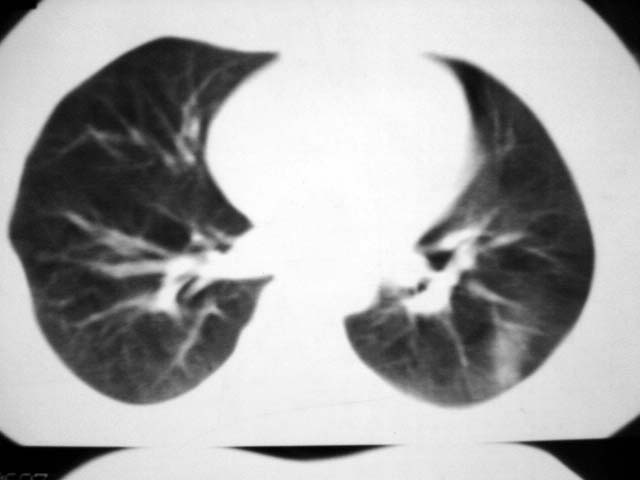

标题: CT12463:女,19岁,炎性假瘤?结核球? [打印本页]

标题: CT12463:女,19岁,炎性假瘤?结核球?

女,19岁,体检时发现。炎性假瘤?结核球?

早产儿,幼时体弱,常感冒肺部感染,13岁后好转。两月前“感冒”后咳嗽两周。

纵隔窗肿块明显较肺窗小,切粗长毛刺,“倒核桃”征:考虑炎性假瘤

病灶肺纵比较大,边缘平直,周围无卫星灶,考虑炎症。建议抗炎治疗后复查。

病灶片状改变,呈钱币样,周围炎性反应明显,考虑球形肺炎可能性大,球形肺炎与炎性假瘤鉴别的重要一点是,炎性假瘤抗炎治疗不会明显改变。

首先要说ct机太差,片子质量不佳,一定是2秒以上机器的作品!其次ct技师需进一步培训,象这种情况就应该针对病灶部位做薄层或高分辨扫描。不过从上传影像看,患者年轻、病灶周围没卫星灶倒支持炎性假瘤诊断,不过象这种部位也有可能是叶间包裹性积液可能。只是ct机太、太差,很难诊断,如一秒机扫描出来90%可直接诊断,有必要时可结合矢状位三维重建。所以要我说建议患者在亚秒(至少是1秒)机上重扫十分有利于正确诊断。

考虑炎症,抗炎后复查。理由:病变肺窗显示的大小明显大于纵隔窗,提示病变周围为密度偏低的渗出改变。不同于结核球和肿瘤。